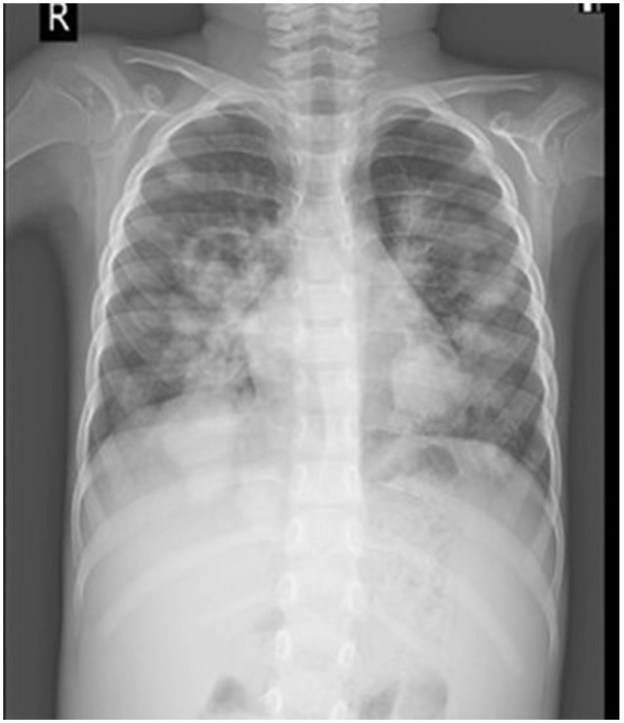

A 6-year-old boy with a known case of acute lymphoblastic leukemia (ALL) in remission presented with recurrent breathlessness, fever, and cough.